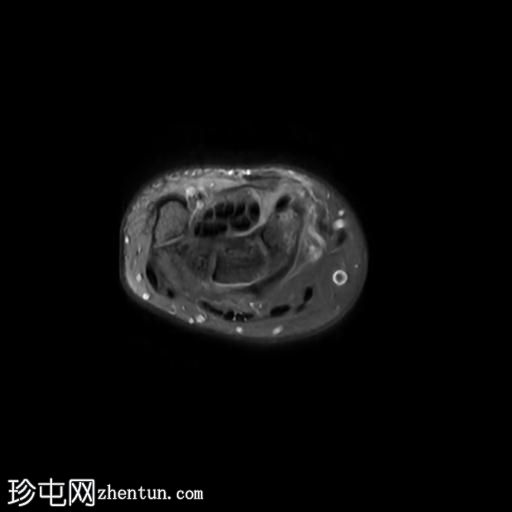

轴位PD序列

脂肪抑制序列